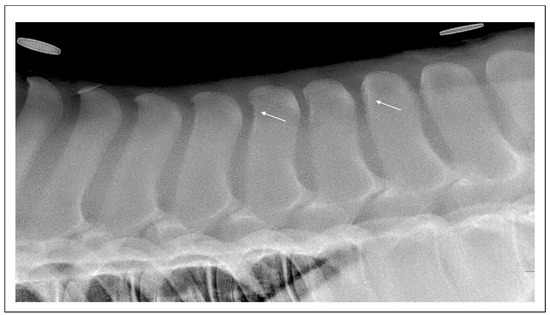

5.2. Diagnostic Imaging Findings